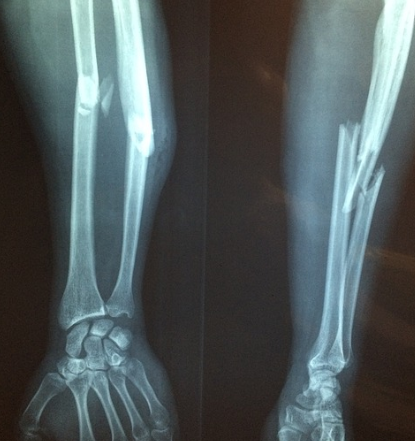

또한 엑스레이 검사를 통해서 골다공증으로 인한 압박 골절 등도 알 수 있습니다.

50대 ~70대 여성은 주로 손목 골절에서부터 먼저 발생하며, 70대에는 고관절이나 척추의 골절이 흔하게 발생합니다.